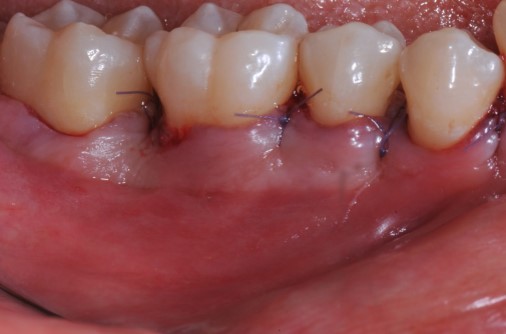

Radiographic view before periodontal regenerative therapy with Straumann® Emdogain®. A deep intrabony defect appeared mesially and distally on the left mandibular first premolar. Pre-surgical probing measured 8 mm. The defect morphology presented as well-contained.